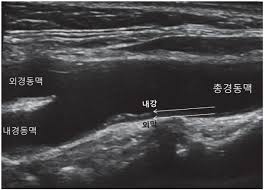

경동맥 협착은 경동맥의 내강이 50% 이상 좁아지는 것을 의미하며, 이로 인해 혈류 속도가 급격히 증가하게 됩니다. 경동맥 초음파 검사를 통해 이러한 협착을 발견할 수 있으며, 70% 이상의 협착이 있는 경우 뇌경색 위험이 급증하므로 즉각적인 조치가 필요합니다. 따라서 경동맥 초음파 검사로 알 수 있는 병 중 협착과 폐색을 조기에 발견하는 것은 매우 중요합니다.

경동맥 죽상경화증은 경동맥의 벽에 콜레스테롤이나 칼슘이 침착되어 두꺼워지는 병입니다. 경동맥 초음파 검사로 알 수 있

는 병 중 가장 흔한 질환으로, 경동맥의 내중막 두께(IMT)를 측정하여 동맥경화증의 진행 여부를 판단할 수 있습니다. IMT가 1mm 이상이면 동맥경화가 진행되고 있다는 것을 의미합니다. 이 질환은 뇌졸중의 위험 요소로 작용하므로 조기 진단이 중요합니다.